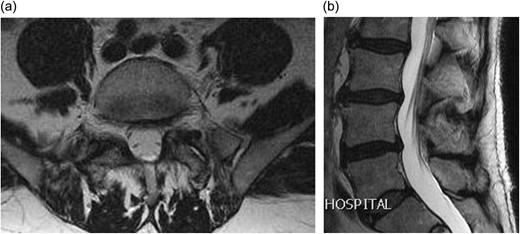

A 66-year-old male presented to our institution with 12 months history of severe back pain and left leg pain in L5/S1 distribution. On examination he had a normal neurology except for a dull left ankle jerk. Magnetic resonance imaging (MRI) of his lumbo-sacral spine showed a left L5/S1 synovial cyst (Fig. 1a and b). The findings and management options were discussed with the patient, who decided for a surgical option. However in view of his recent cardiac history it was decided to see him again in clinic in 6 months’ time. After reviewing him in clinic, he was added to the surgical waiting list and as his MRI scan was a year old, fresh set of scans was requested nearer to his operation date. Surprisingly his repeat MRI showed complete resolution of the L5/S1 synovial cyst (Fig. 2a and b).

(a) Axial T2 weighted MRI showing complete resolution of the synovial cyst; (b) sagittal T2 weighted MRI showing complete resolution of the synovial cyst.